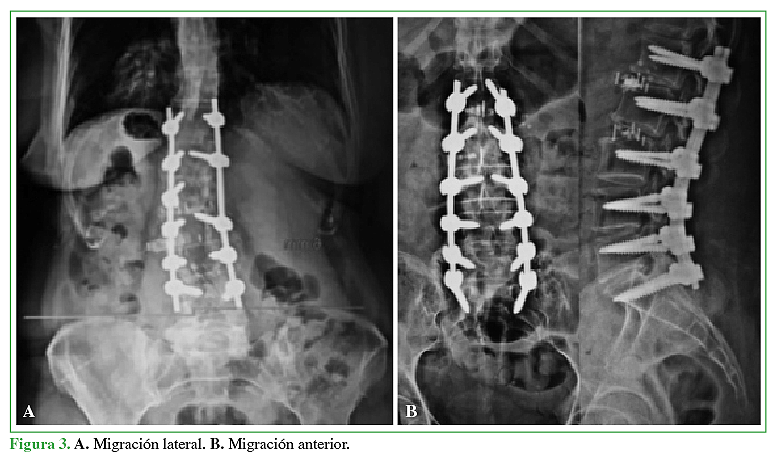

Daffner SD, Wang JC. Migrated XLIF cage: case report and discussion of surgical technique. Orthop. 2010,33:518.

Towers WS, Kurtom KH. Stand-alone LLIF lateral Cage Migration: Acase report. Cureus 2015, 7(10) e347.